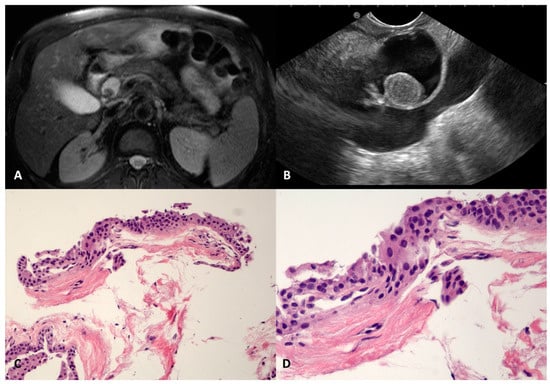

SCOP is a very rare benign pancreatic cyst that has been recently described; it is usually well defined and unilocular, probably due to the dilation of a branch-duct with metaplastic squamous transformation [,]. In our series, four SCOPs were found, three in the head (22, 22, and 32 mm) and one in the body (40 mm) of the pancreas. They were regular, had a thin and fibrotic wall, and had a homogeneous anechoic content, except in one case, where a round-shaped avascular intracystic nodule was documented in both magnetic resonance imaging (MRI) and EUS (Figure 3A,B). In two cases, the levels of CEAs were elevated in the cyst fluid cytology. The TTNB retrieved fragments of a simple stratified squamous epithelium, without keratinization, lining the thin fibrous cyst wall (Figure 3C,D).

Figure 3.

Squamoid cyst of pancreatic ducts. T2-weighted magnetic resonance imaging of a pancreatic cyst located in the head, with a nodule inside (A). The same cyst on an endoscopic ultrasound scan containing round vegetation that resulted in avascular at contrast-harmonic evaluation (B). The fibrous thin wall of the cyst is lined by stratified epithelium (C) without atypia and keratinization (D). Hematoxylin–eosin original magnification ×100 (C), ×200 (D).

Due to the rarity of this cyst and the lack of information about its preoperative diagnosis, as well as the presence of thickened walls and increased CEA levels in the intracystic fluid analysis, two of the SCOPs were resected, given the persistent suspicion of the mucinous nature of the cyst despite the TTNB result. The surgery confirmed the diagnosis of the above-mentioned benign condition.